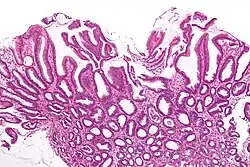

| Micrograph of a reactive gastropathy. H&E stain. | |

- Foveolar hyperplasia (black arrow), as a tortuosity in the "neck" region of the gastric glands.

- Scant or minimal inflammatory cells (white arrow), i.e. lack of large numbers of neutrophils and plasma cells..

- Smooth muscle hyperplasia in the lamina propria (in black oval).

The diagnosis is by examination of tissue, e.g. a stomach biopsy.

Low mag. Low mag.